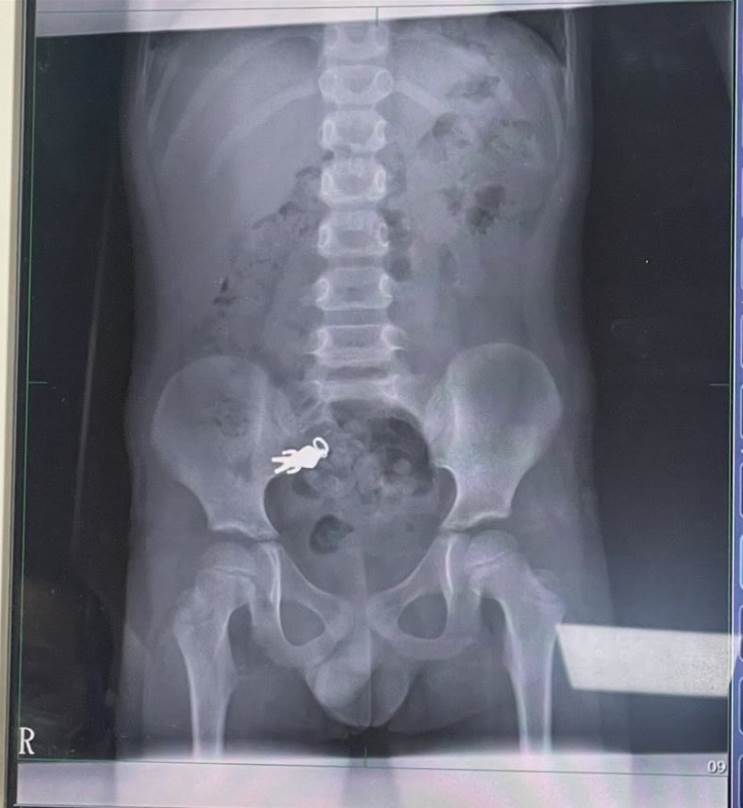

8歲童誤吞2公分「超人力霸王」。(圖/記者黃國瑞攝影)

羅東博愛醫院小兒科主任謝錦桐分享此個案。他說這起意外發生在上週六,男童因為一心二用,在觀看電視節目的同時享用餅乾,不慎將隨身攜帶的超人力霸王吊墜公仔誤食。家長隨即將孩子送往本院進行檢查,進行X光檢查,影像清晰顯示男童腹部有一個公仔形狀的異物,還能看出上面帶有吊環的特徵。